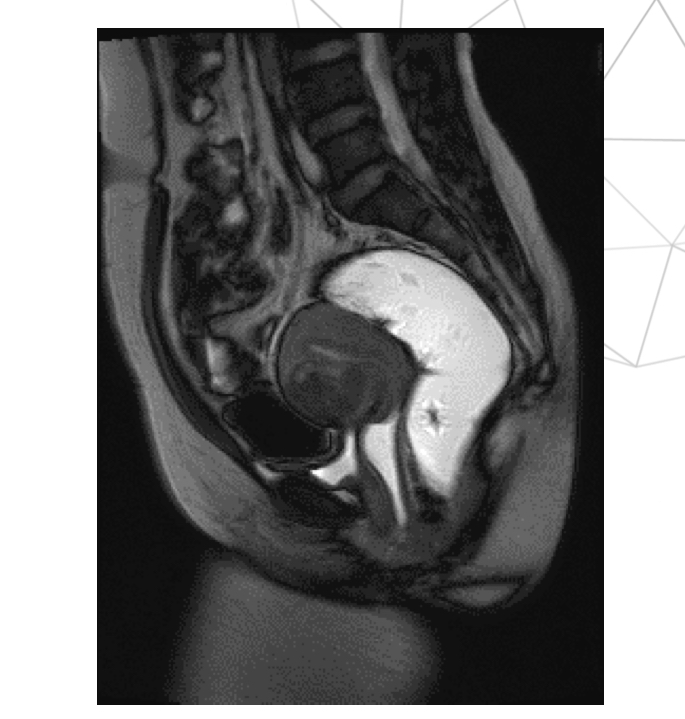

T2 TRUEFISP, mid sag, thì nhíu

T2 TRUEFISP mid sagittal, thì rặn